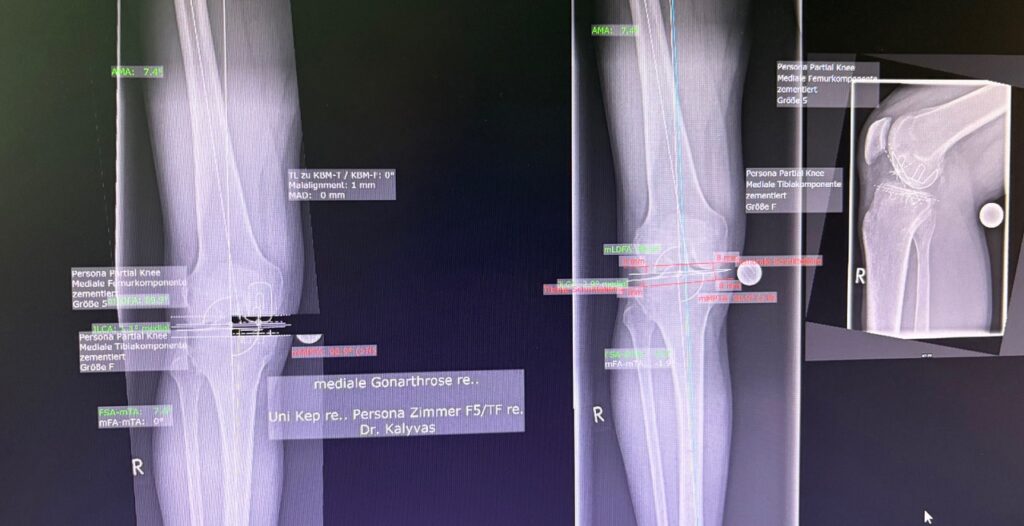

Η ημιολική αρθροπλαστική γόνατος (partial / unicompartmental knee replacement) είναι επέμβαση όπου αντικαθίσταται μόνο το φθαρμένο διαμέρισμα του γόνατος και όχι ολόκληρη η άρθρωση.

Πώς γίνεται

- Μικρότερη τομή από την ολική

- Αντικατάσταση μόνο του πάσχοντος διαμερίσματος

Η επιτυχία της ημιολικής αρθροπλαστικής εξαρτάται κυρίως από:

- σωστή διάγνωση

- εμπειρία χειρουργού

- ακριβή τοποθέτηση (συχνά με ρομποτική υποβοήθηση)

Η τελική επιλογή της χειρουργικής τεχνικής γίνεται μετά από αναλυτική κλινική αξιολόγηση και προσεκτικό προεγχειρητικό σχεδιασμό, με στόχο το βέλτιστο και ασφαλέστερο αποτέλεσμα για τον ασθενή. Απαραίτητη προϋπόθεση για την επίτευξη εξαιρετικών αποτελεσμάτων αποτελεί η εξειδίκευση του χειρουργού στη συγκεκριμένη τεχνική, καθώς και η εκτεταμένη εμπειρία με μεγάλο αριθμό επεμβάσεων. Ο έμπειρος ορθοπαιδικός Νικόλαος Καλύβας εφαρμόζει την Ημιολική αρθροπλαστική γόνατος (Μονοδιαμερισματική) επί σειρά ετών στη Γερμανία, έχοντας χειρουργήσει μεγάλο αριθμό ασθενών. Τα τελευταία χρόνια, από τη θέση του Αναπληρωτή Διευθυντή σε ένα από τα μεγαλύτερα κέντρα αρθροπλαστικής της Γερμανίας, είχε ενεργό ρόλο στην εκπαίδευση ειδικευομένων ορθοπαιδικών στη συγκεκριμένη τεχνική.